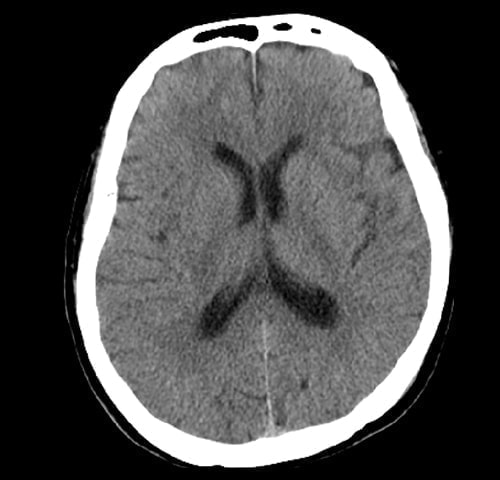

・ 脳(脳出血・脳梗塞・脳腫瘤)病変

脳